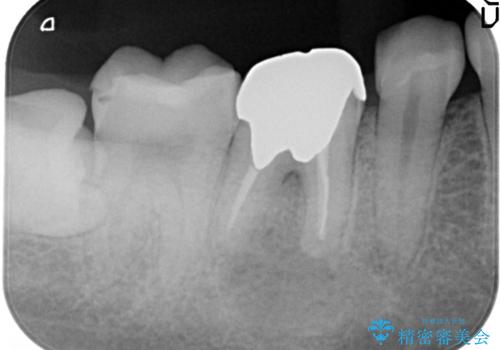

- 奥歯がズーンと痛いことを主訴に来院されました。

根管治療時に穿孔部位を認め、MTAにて修復し、分岐部の歯周ポケットおよび骨欠損に対しては、再生治療を行うことで、正常な歯周状態の獲得ができました。

歯冠修復はオールセラミッククラウンで行なっております。